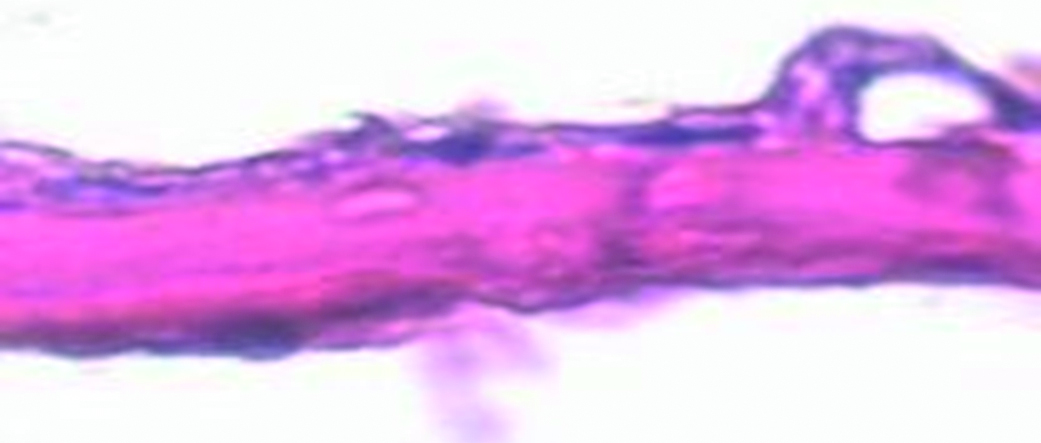

The spongy layer in this sample group shows the least damage. Collagen fibers are thin, multidirectional, and loosely arranged. This preparation clearly demonstrates the end-to-end porosity of the biomaterial. The isolated homogeneous formations attached to collagen fibers are present (Fig. 10).

Figure 10. Electron microscopic image of amniotic membrane in a scanning electron microscope. Spongy layer of the preparation of lyophilized amniotic membrane without preliminary impregnation with glycerol. Magnification x1000.

Рисунок 10. Электронно-микроскопическое изображение амниотической мембраны в сканирующем электронном микроскопе. Спонгиозный слой препарата лиофилизированной амниотической мембраны без предварительного пропитывания глицерином. Ув. х1000.